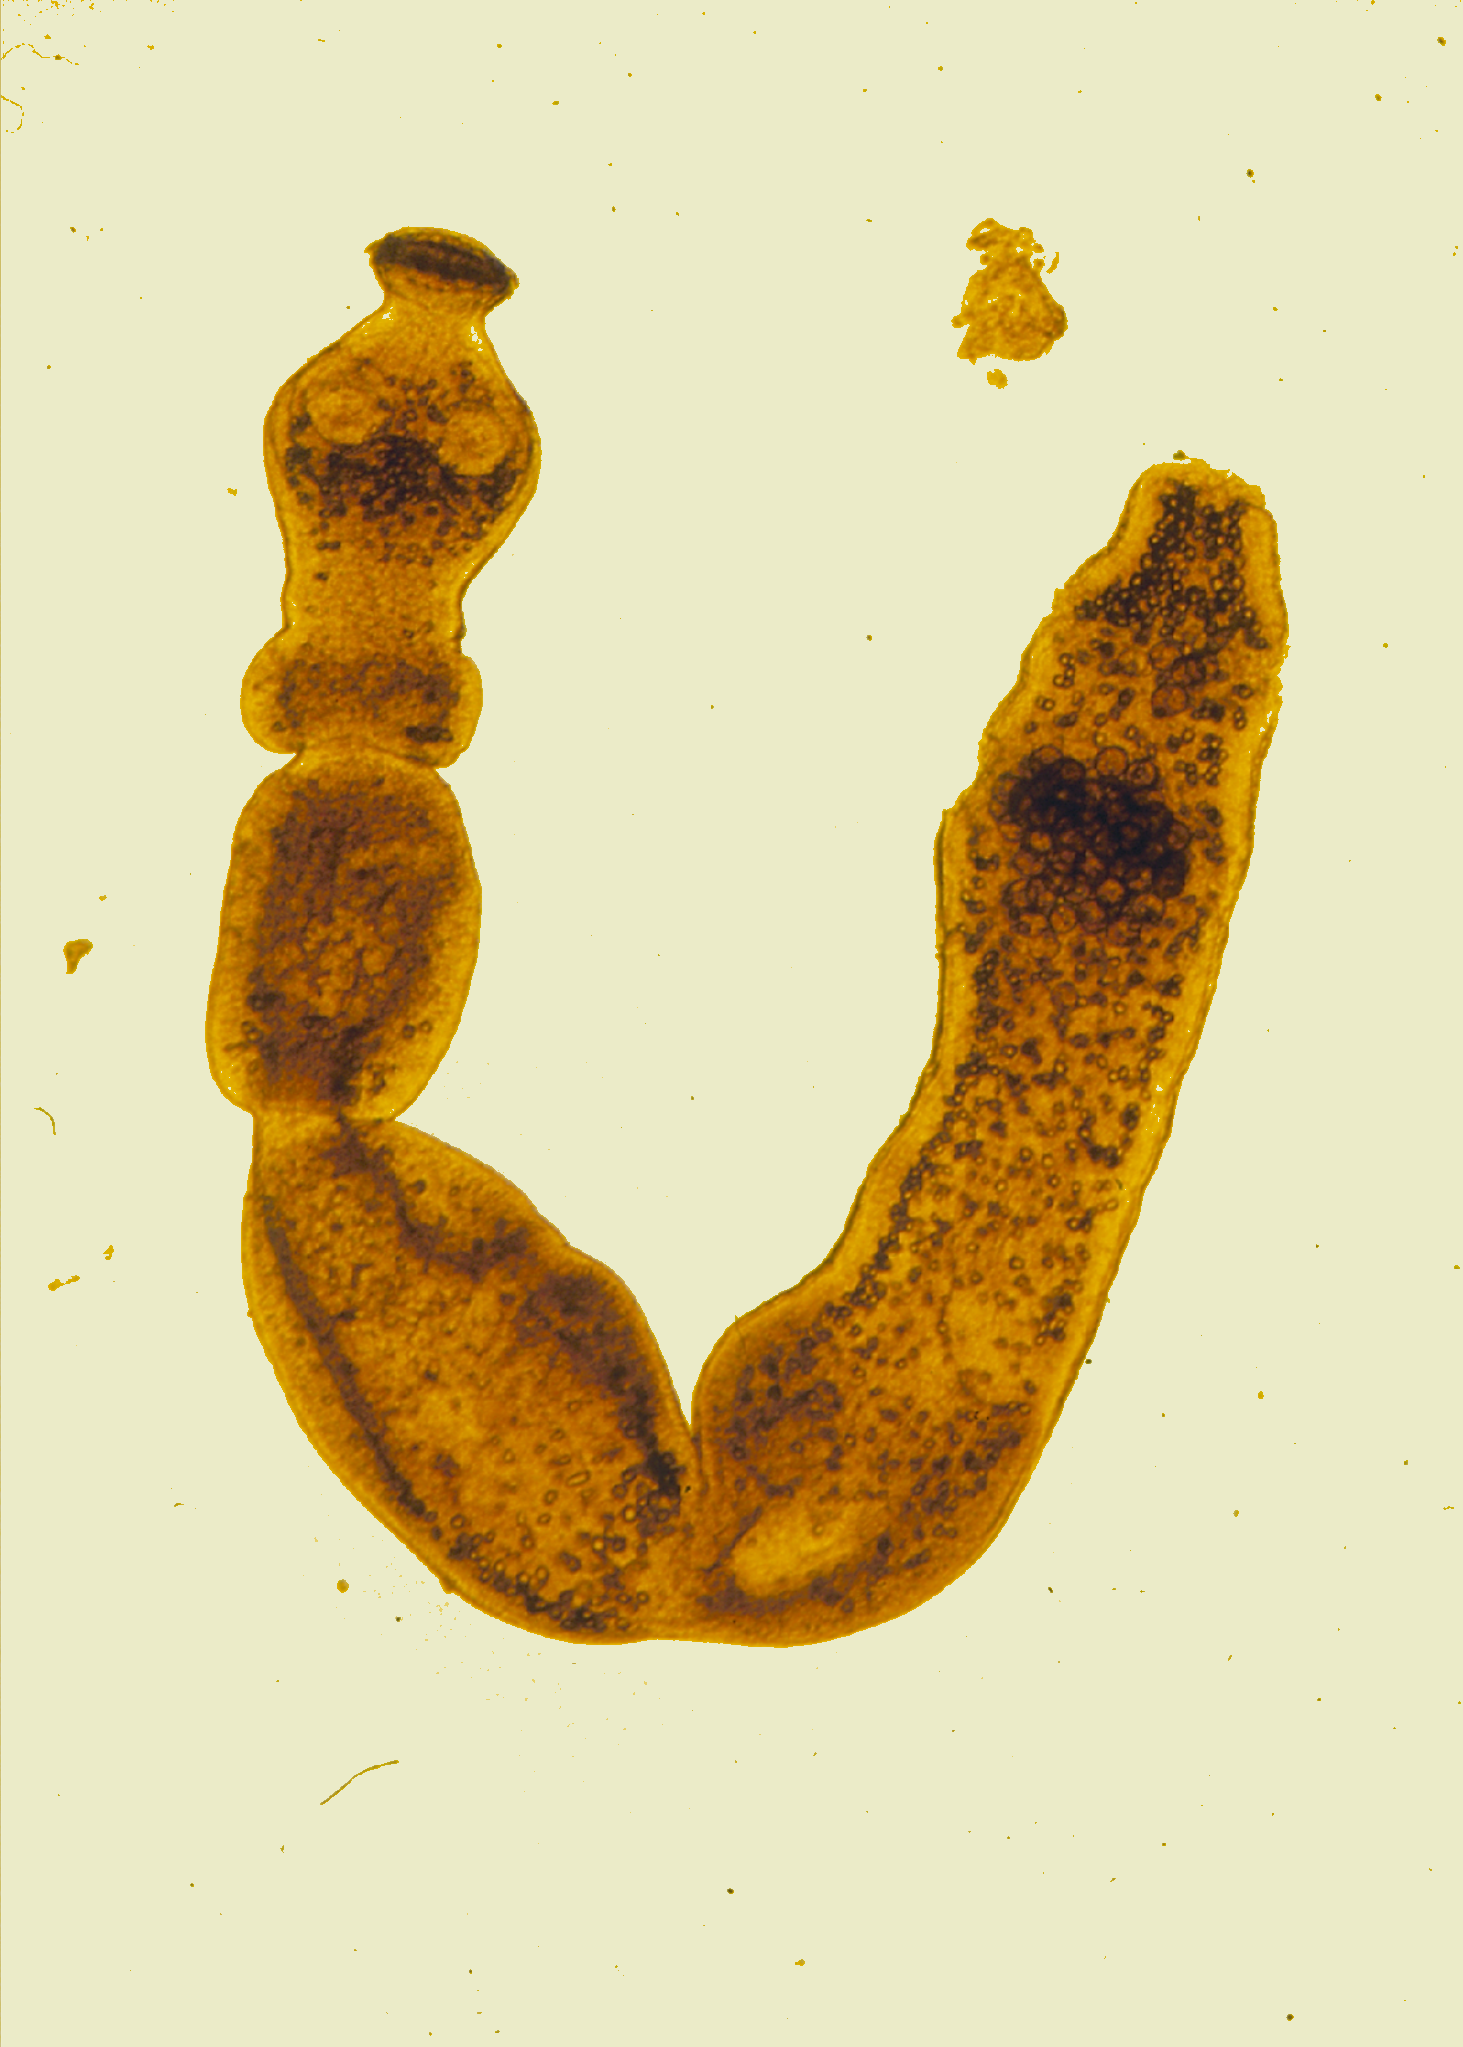

Bei dem in Alkohol eingelegten Präparat handelt es sich um Larven und Zysten in einem menschlichen Leber¬tumor. „Diese verblüffende Entdeckung haben wir nun in unserer aktuellen Studie genutzt, um die Systematik der Gattung Echinococcus und die systematische Stellung des humanme¬dizinisch relevanten Fuchsbandwurms zu klären“, fügt Ernst hinzu. Durch den Einsatz von Next-Generation-Sequencing-Technologien gelang es dem Forschungsteam, das mitochondriale Genom von Echinococcus multilocularis vollständig zu entschlüsseln. Es umfasst 13.738 Basenpaare und enthält 12 Gene für Proteine, sowie je 2 rRNA- und 22 tRNA-Gene. Die Untersuchung zeigte zudem, dass der Fuchsbandwurm eng mit Echinococcus shiquicus verwandt ist. Dieser parasitische Bandwurm nutzt als Endwirt den ausschließlich auf dem tibetanischen Hochplateau beheimateten Tibetfuchs. Die genetische Linie, der das wiedergefundene Typusexemplar von Echinococcus multilocularis angehört, bestehe seit mehr als 200 Jahren, heißt es in der Studie.